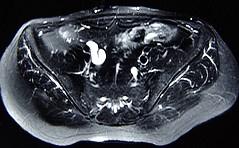

问题 女,31岁,右侧腰部胀痛不适,MRI检查如图所示,下列说法正确的是 ( )

选项 A、左肾输尿管未见异常 B、考虑为右侧输尿管囊肿 C、右侧输尿管粗细不均并迂曲扩张 D、右侧输尿管下段呈囊样扩张 E、右肾重度积水

答案 ABCDE